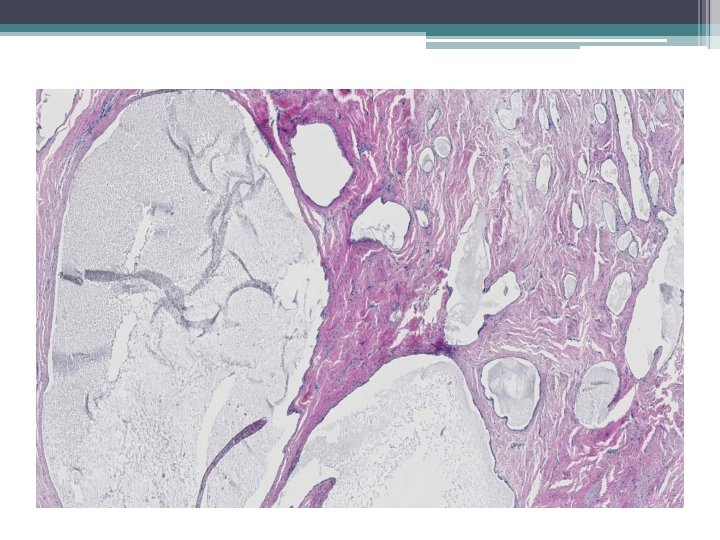

Mikro:

Ektopická prostatická tkáň • • vzácně lokalizace: cervix, vagína věk 21 -65 let mikroskopicky : tubuly a aciny některé papilární, některé kribriformní, s dlaždicovou metaplázií

• Mikroskopicky: • dobře ohraničená hnízda s vrstevnatým dlaždicovým epitelem a tubuly vystlané jednou až dvěma řady kubických buněk, nebo dlaždicovými buňkami. V centru hnízd může byť přítomná nekróza s kalcifikací, nebo keratinové perly.